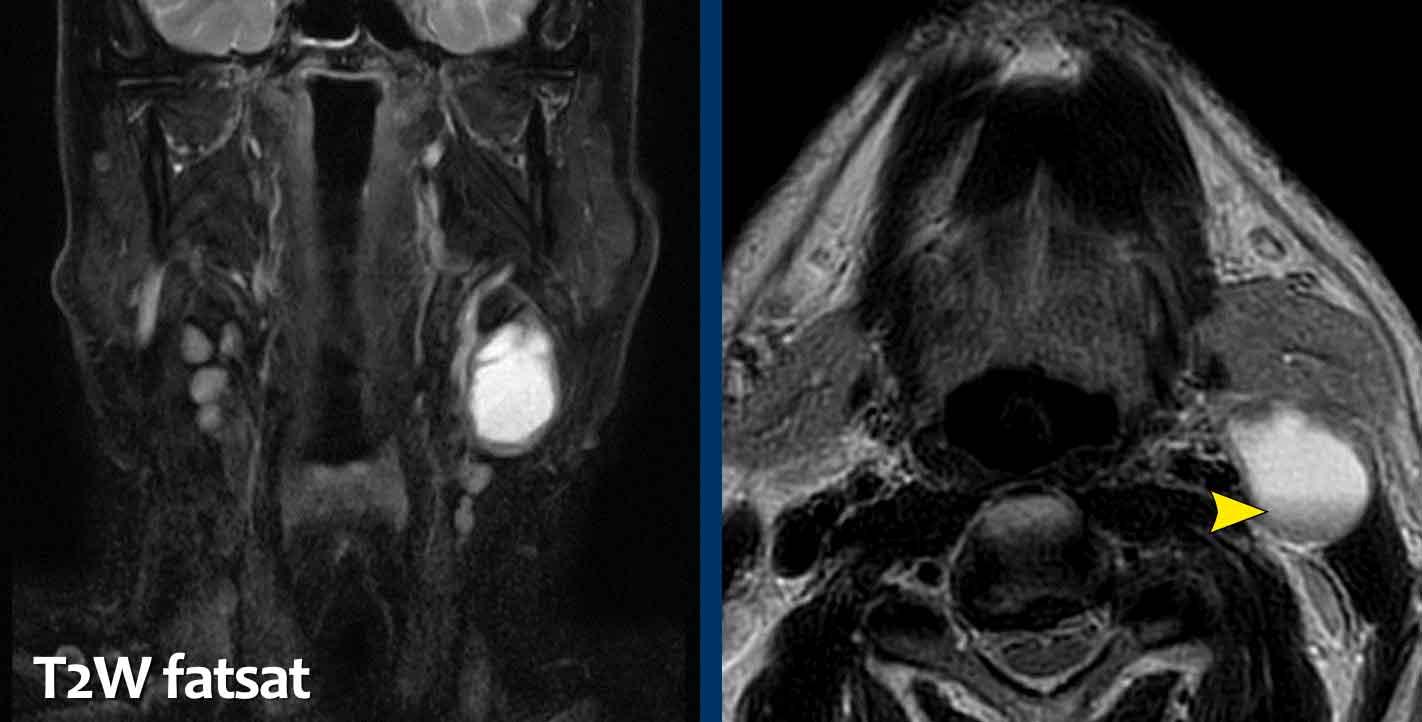

Các hình ảnh này thuộc về một nam bệnh nhân 59 tuổi, có tiền sử hút thuốc lá, nhập viện vì sưng vùng cổ.

Báo cáo MRI ban đầu ghi nhận có một tổn thương dạng nang nằm phía sau tuyến dưới hàm và phía trước cơ ức đòn chũm; không có hạch bạch huyết kèm theo.

Chẩn đoán có khả năng nhất: nang khe mang.

Đây có vẻ là một kết luận hợp lý vì vị trí điển hình của nang khe mang (loại hai) là nằm giữa tuyến dưới hàm và cơ ức đòn chũm.

Tuy nhiên, tuổi của bệnh nhân là một dấu hiệu cảnh báo quan trọng.

Năm tháng sau, khối sưng trở nên đau.

MRI được chụp lại.

Các phát hiện bao gồm:

- Có hiện tượng ngấm thuốc tương phản từ ở thành nang và trong các mô mềm xung quanh.

- Không có hạn chế khuếch tán.

Các phát hiện này được cho là hậu quả của nhiễm trùng và khả năng di căn dạng nang ít có khả năng hơn, nhưng không thể loại trừ, đặc biệt do tuổi của bệnh nhân.

Bệnh nhân được điều trị bằng kháng sinh và một tháng sau tổn thương được phẫu thuật cắt bỏ.

Kết quả giải phẫu bệnh xác nhận đây là nang khe mang.

Nang khe mang điển hình là các tổn thương dạng nang có thành mỏng.

Tuy nhiên, di căn dạng nang có thể bắt chước hình ảnh nang khe mang.

Đặc biệt là di căn hạch bạch huyết của ung thư tuyến giáp thể nhú và ung thư hầu họng (liên quan đến HPV).